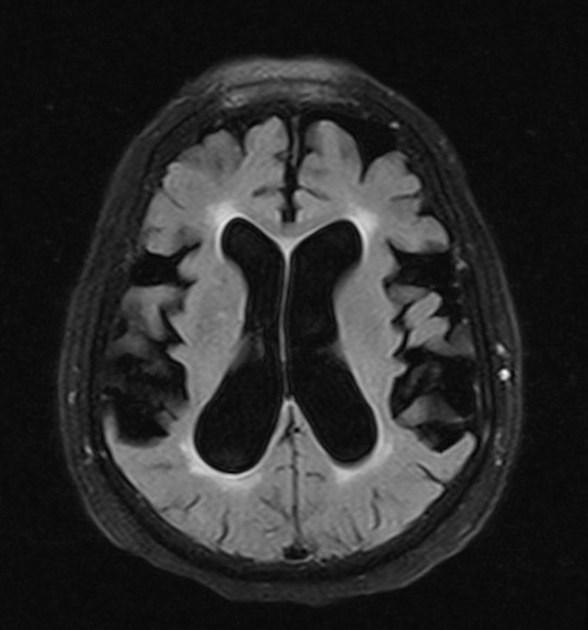

CADASIL/CARASIL

cerebral autosomal dominant/recessive arteriopathy with subcortical infarcts and leukoencephalopathy

NOTCH3 mutations

causes progressive cognitive decline, recurrent ischemic strokes (often lacunar), migraines

MRI features symmetric WM hyperintensities, including in anterior temporal poles